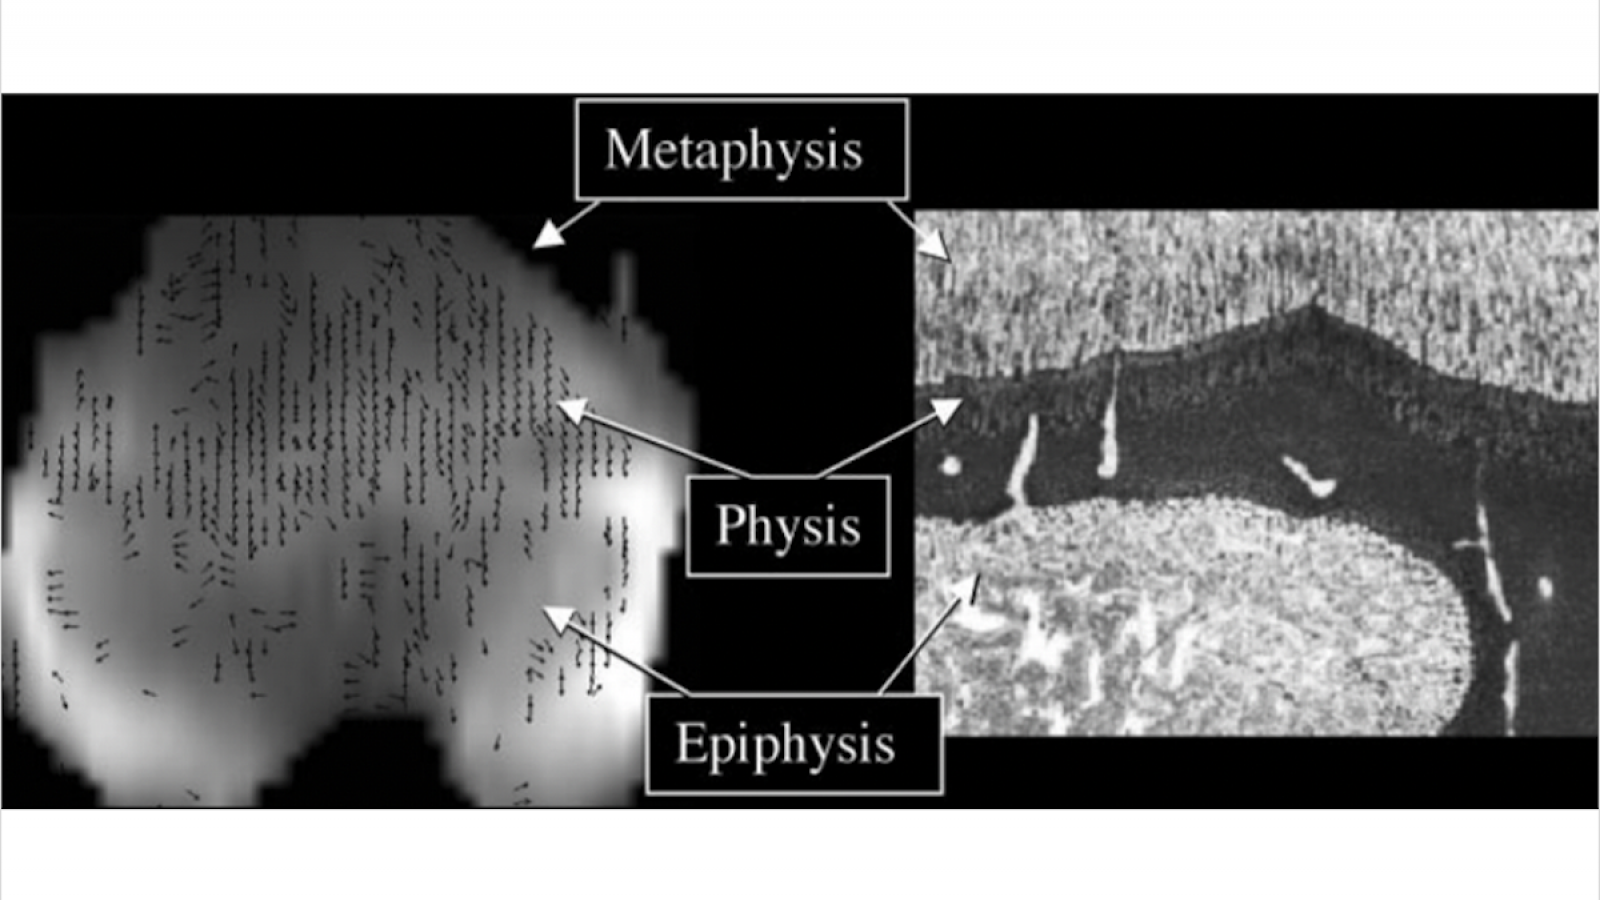

Validation of Diffusion Tensor Imaging of the Physis and Metaphysis as Predictor of Skeletal Growth in Children

- Summary: Tract volume derived from DTI of the physis/metaphysis can predict height velocity (1-yr. height gain) and total height gain more accurately and precisely than current bone age-based methods.

Deep Learning Assisted Diffusion Tensor Imaging for Evaluation of the Physis and Metaphysis

- Summary: We have performed a study to compare manual segmentation by several observers with automated segmentation performed using a 3D U-net network. Our hypothesis is that the automated segmentation can provide comparable results to the manual process with a significant gain in time.